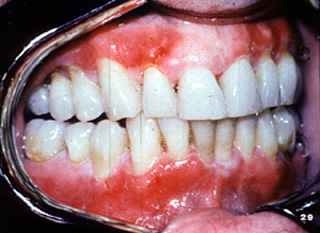

Aquí hay  áreas de ulceración y descamación gingival.